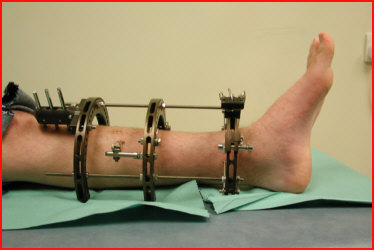

This is a 14 year old boy who caught his ski in the mesh of a dry ski slope and sustained a tibial fracture with a large anterior butterfly. This was stabilised with the Sheffield Hybrid Fixator. As the fracture line was very steep (81 degrees), additional fixation was required but safe soft tissue corridors contraindicated compressive olive wires, and so the arched wire technique was employed. Although immediate postoperative weightbearing was advised he was afraid to load the leg until one morning around 4 weeks post injury, where he suddenly found himself walking pain free. Since then, he was able to fully weightbearing without discomfort (picture taken at 6 weeks post-op). The arched wires and middle ring were removed for dynamisation at 11 weeks and the frame was removed at 15 weeks. He has had an excellent radiological and functional outcome. |